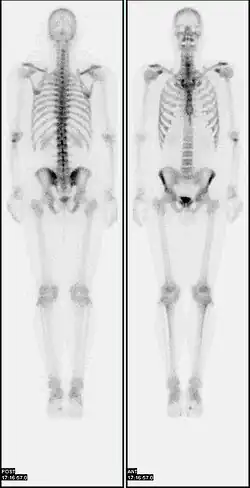

A nuclear medicine whole-body bone scan. The nuclear medicine whole-body bone scan is generally used in evaluations of various bone-related pathology, such as for bone pain, stress fracture, nonmalignant bone lesions, bone infections, or the spread of cancer to the bone.

A bone scan or bone scintigraphy /sɪnˈtɪɡrəfi/ is a nuclear medicine imaging technique used to help diagnose and assess different bone diseases. These include cancer of the bone or metastasis, location of bone inflammation and fractures (that may not be visible in traditional X-ray images), and bone infection (osteomyelitis).[1]